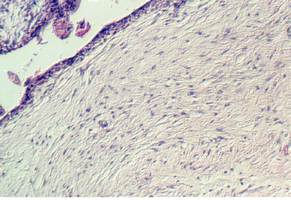

Look at the maternal side of the placenta, where ANCHORING VILLI can be seen embedded in uterine epithelia.  The DECIDUAL BASALIS with the DECIDUA cells are found in the endometrium. Anchoring villi are shown in the following photographs.

placenta_old.jpg (71791 bytes)placenta_old2.jpg (67701 bytes)